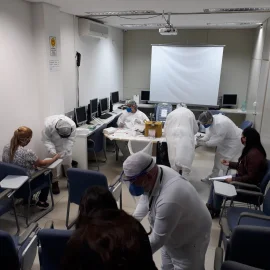

Governo de SP inicia testagem para Covid-19 na rede estadual de ensino

Secretaria de Saúde realiza testagem de Covid-19 no Distrito de Tibiriçá

Mais 238 servidores públicos são testados para Covid-19 em Bauru

Servidores da Funprev são testados para a Covid-19

Servidores públicos realizam testes de Covid-19, nesta segunda-feira (24)

Servidores públicos de Bauru são testados para Covid-19; mais de 20 positivaram

Prefeitura inicia aplicação de testes de Covid-19 em servidores públicos